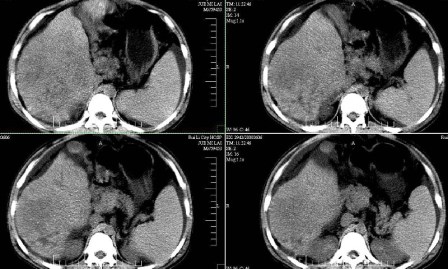

标题: CT13930:M,33岁,腹胀、腹痛10天余。 [打印本页]

标题: CT13930:M,33岁,腹胀、腹痛10天余。

右上腹压痛,肝大,质硬。腹水征。ct:肝右叶(后段)低密度影,性质待定。

肝硬化、腹水,肝右叶低密度首先考虑肝癌可能,左叶低密度不除外转移可能。建议增强检查。

肝硬化、大量腹水,肝右叶巨大肿块,境界欠清,中间见不规则低密度坏死区,考虑肝癌应该问题不大,至于肝左叶低密度灶是否转移应该意义不是很大了,慎重起见还是建议增强扫描。